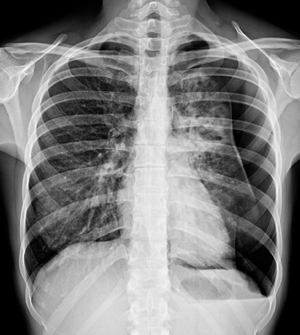

What's your diagnosis??!!

1.pleural effusion 2.pneumothorax 3.pulmonary edema 4. sarcoidosis 5.emphysema

2...air is black on radiography whilst fluid is white.